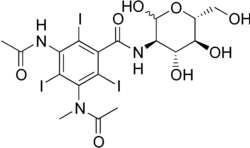

| Other names | 3-aAcetamido-2,4,6-triiodo-5-(N-methylacetamido)-N-[(3R,4R,5S,6R)-2,4,5-trihydroxy-6-(hydroxymethyl)oxan-3-yl]benzamide |

| Formula | C18H22I3N3O8 |

| Molar mass | 789.100 g·mol−1 |